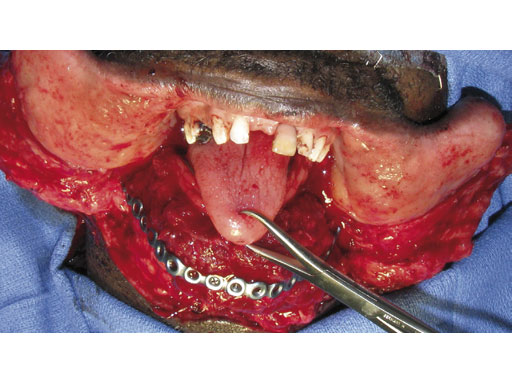

Case 1: A 47-year-old man transferred to the authors hospital approximately 10 days following the resection of a large, benign, locally aggressive odontogenic tumor of the mandible. He was primarily reconstructed with a locking reconstruction plate. The plate dehisced and the patient was unable to eat or swallow leading to his emergent admission to the authors hospital for reconstruction of his mandible with a composite vascularized flap (fibula). The initial internal hardware was removed and a 2.5 mm matrix mandible locking reconstruction plate contoured and applied to the remaining mandibular rami to aid in the reconstruction of the subtotal mandibular defect.

Fig 4 After removal of the reconstruction plate, a new 2.5 mm mandible matrix reconstruction plate is contoured to restore the continuity of the mandible.

Fig 6 The fibula flap is contoured and inset to restore mandibular continuity and the skin paddle is used to restore the intraoral soft-tissue defect.